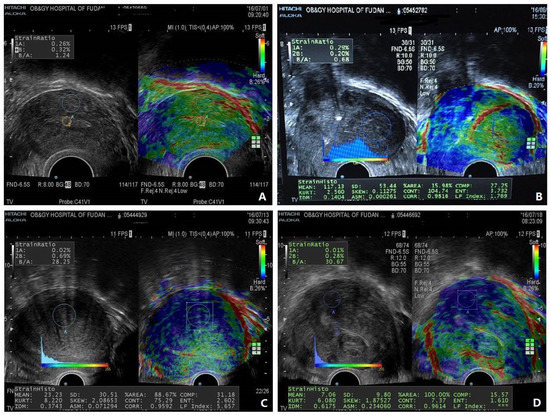

In Search of an Imaging Classification of Adenomyosis: A Role for Elastography?

Source : https://www.mdpi.com/2077-0383/12/1/287

Adenomyosis is a complex and poorly understood gynecological disease. It used to be diagnosed exclusively by histology after hysterectomy; today its diagnosis is carried out increasingly by imaging techniques, including...

Conclusions: Through imaging tissue biomechanics, elastography adds a completely new dimension to the detection of adenomyosis and its associated pathology. This is primarily due to the fact that the resultant imaging reflects the composition and organization of the microstructure underlying uterine pathology in general and adenomyosis in...